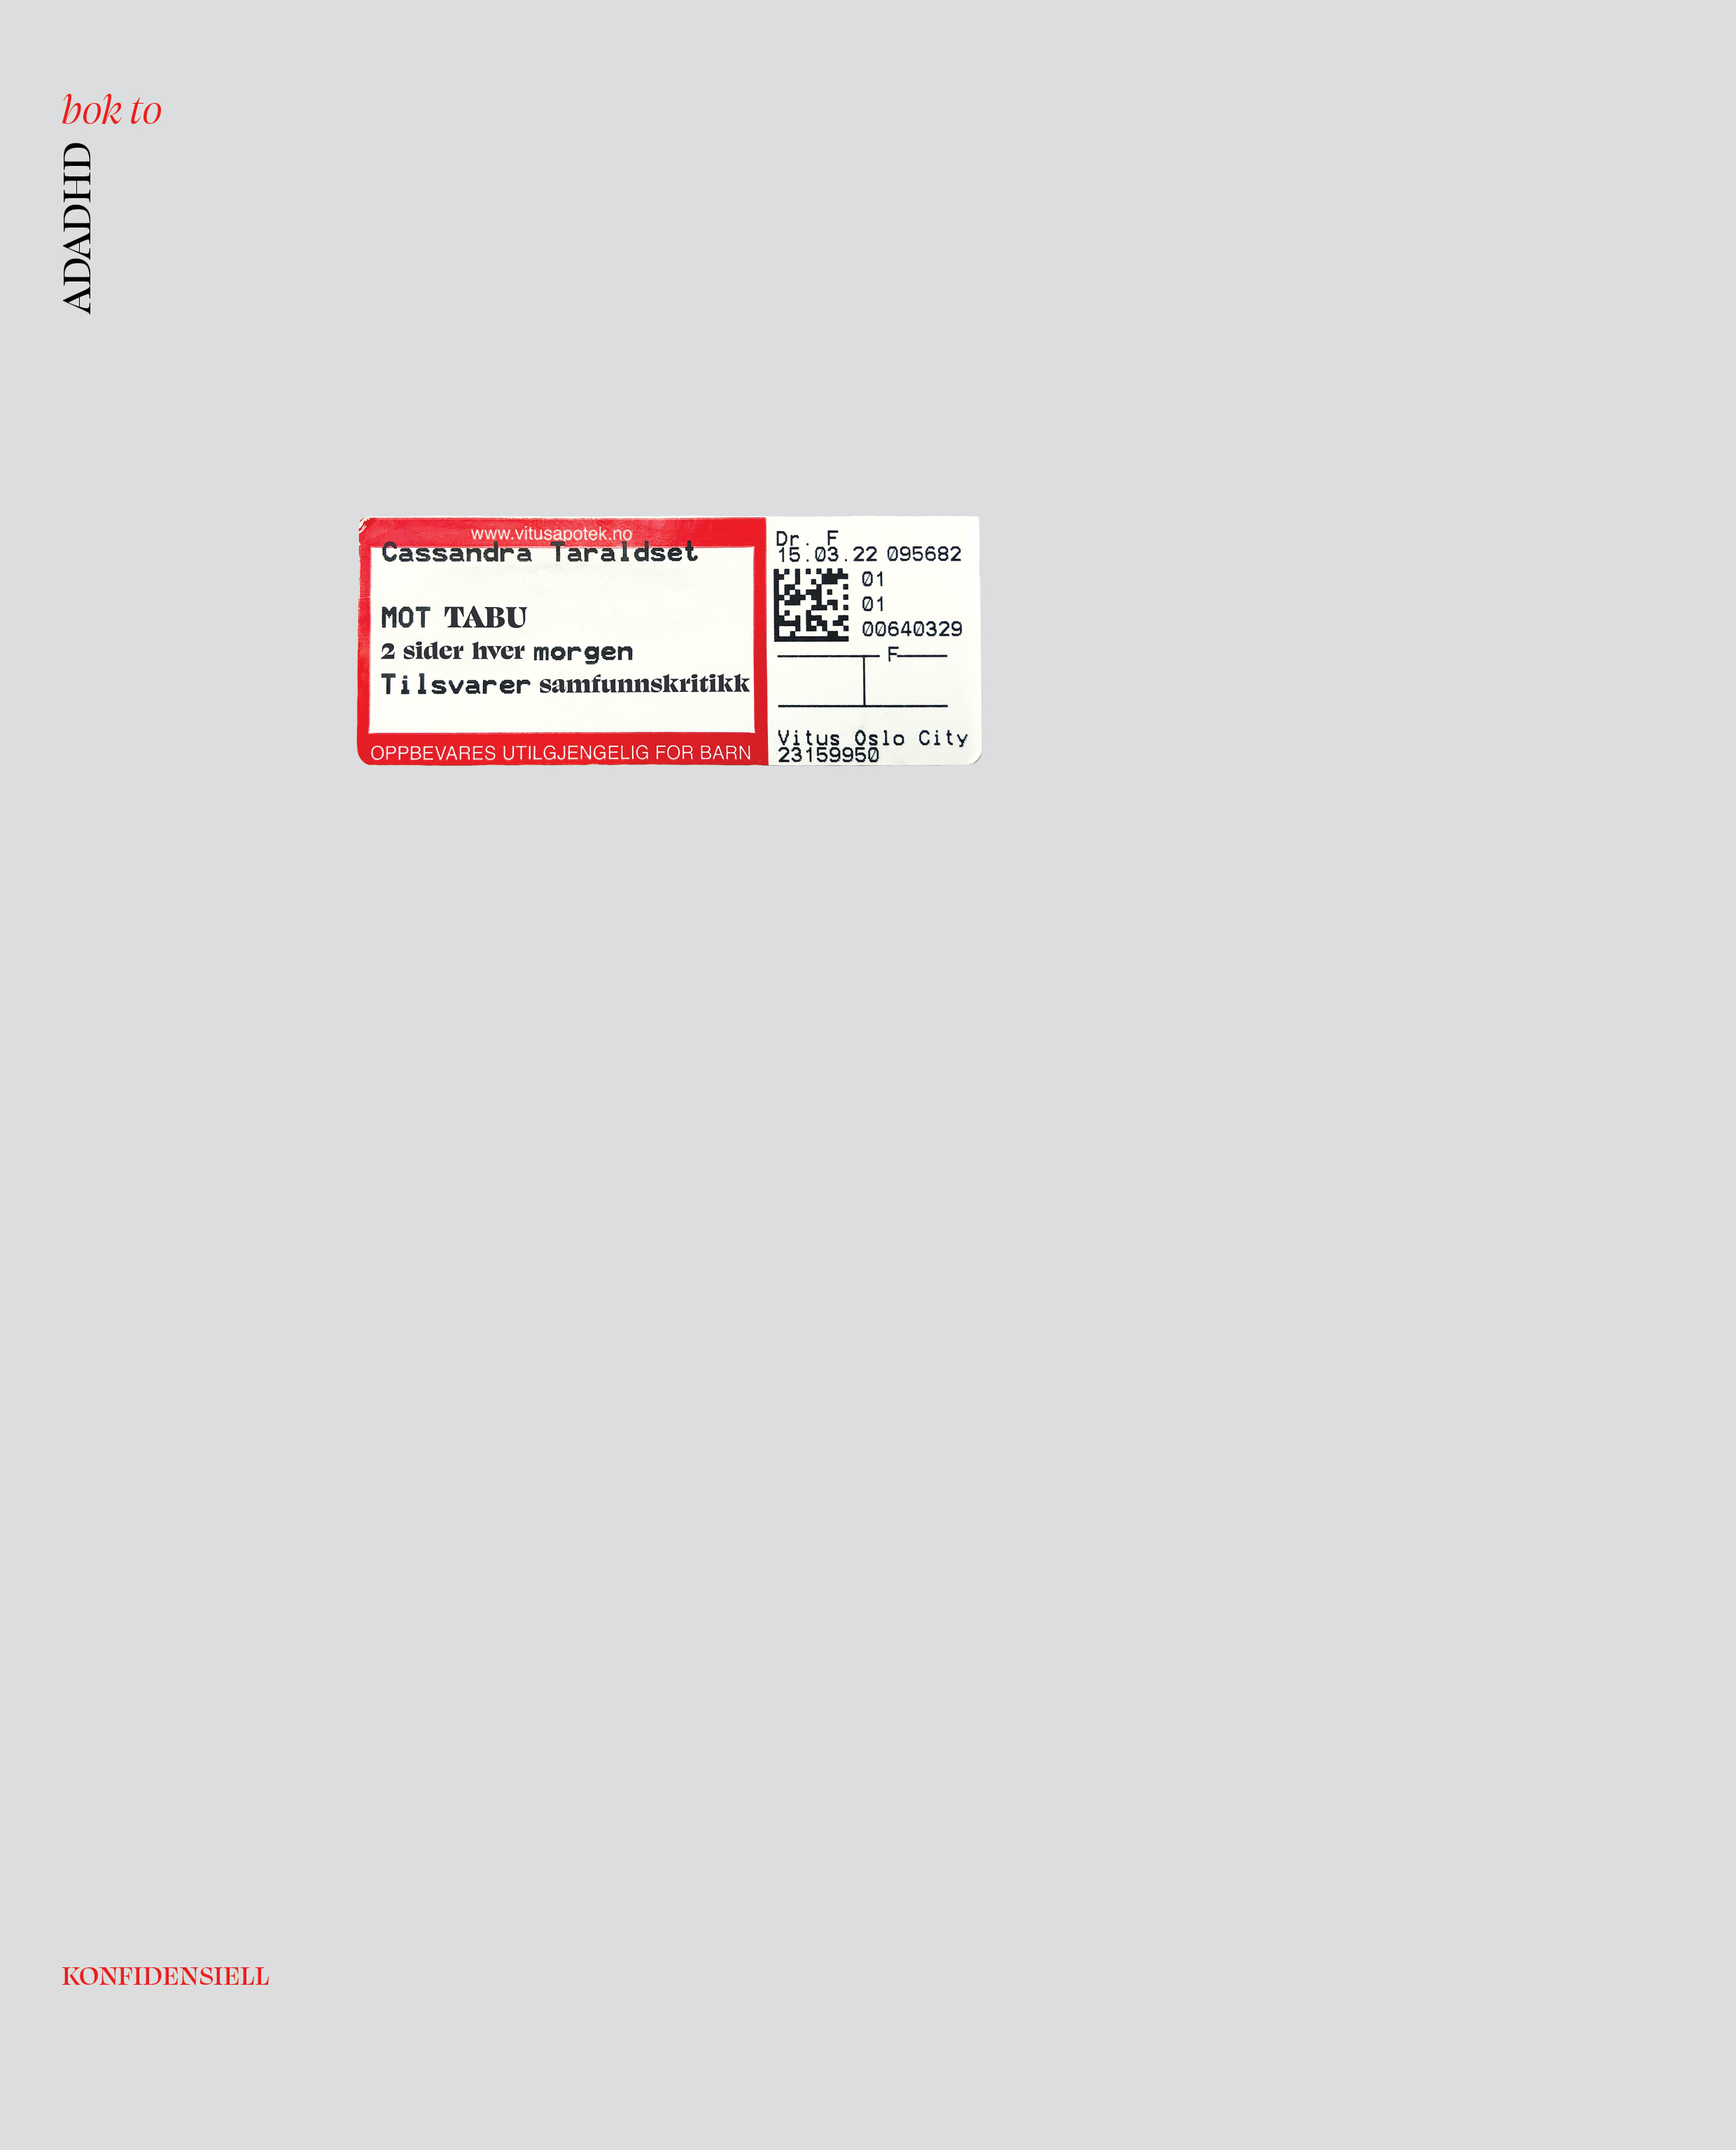

Bok 1

Bok 2

Bok 2

copyright: Cassandra Taraldset